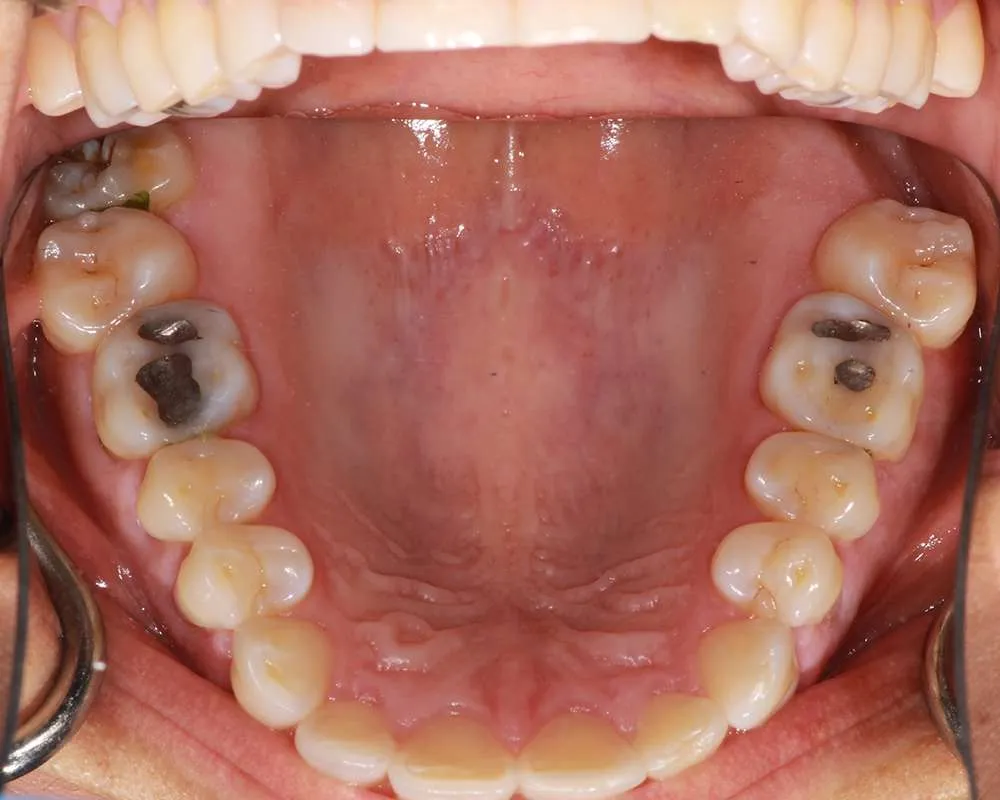

Real Stories, Real Results: Case Studies Showcasing How Our Personalized Approach Transforms Smiles and Lives

Complex Cases

Witness the Remarkable Changes We Can Achieve